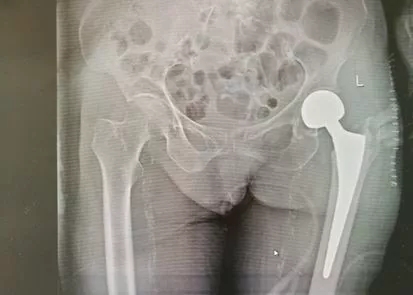

经检查,李奶奶被诊断为:左股骨颈骨折。王开颜主任向李奶奶家属介绍:股骨颈骨折俗称“髋部骨折”, 髋部骨折的老人在未及时得到正确治疗后,因长时间卧床容易引发肺部感染、褥疮、深静脉栓塞、肺栓塞等并发症,危及生命,所以髋部骨折也常被称为“临终骨折”。该类骨折的老人若想重新站立起来,手术治疗是积极的、最佳的治疗方案。但在临床中,经常会出现患者家属担心老人年纪太大承受不了手术而选择保守治疗,也有许多医院因为患者年纪大而不愿承担风险,拒收高龄患者。“王主任,我们来之前就听说不少高龄骨折老人经过贵院的妙手施治,重新步入了幸福晚年,我妈交给你们我放心,请大胆为其手术治疗!”李奶奶的儿子满怀信心回复王开颜主任。患者及家属的信任是医生最大的动力,但要给96岁的高龄老人手术,对医生、患者及其家属都是一场考验。因为李奶奶系高龄骨折患者,身体虚弱,骨质疏松严重,还伴有2级高血压、冠心病等多种基础疾病,术中及术后出现并发症的风险极高。为确保手术顺利进行,王开颜主任立即向医务科汇报,医务科召集综合内科、麻醉科、手术室等多科室专家对李奶奶病情及身体状况进行了会诊和术前评估,并制定了周密详细的手术方案及应急处理方案。经过前期专业治疗和调理,在李奶奶身体状况达到手术最佳状态时,由刘卓华院长亲自主刀、关节科专家团队为其施行了左侧髋关节置换术,不到40分钟,手术顺利完成。

术后,刘卓华院长定期查房,关节科医护人员对李奶奶进行密切观察,并叮嘱其注意休息,加强营养,适当进行功能锻炼…在精心呵护下,李奶奶各项生命体征平稳,精神状态良好,第二天下午,便在家属的搀扶下下床走动。